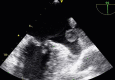

Figures